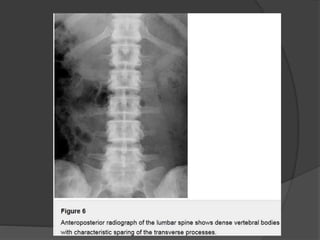

Dense vertebral bodies with characteristic sparing of the transverse

processes is seen.